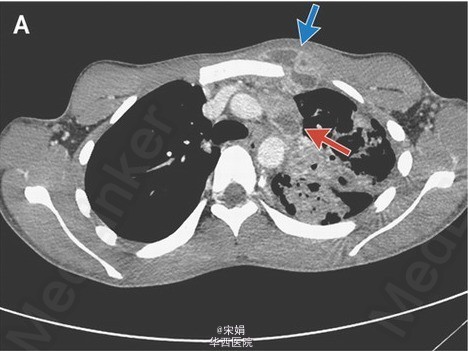

18岁男性,咳嗽3+月,伴淡红色痰、体重下降、发热。一周内前胸壁出现一局限性红肿。胸部CT示哑铃型脓肿(皮下脓肿通过窦道与深部脓肿相通:前胸壁皮下脓肿→左侧纵膈淋巴结内脓肿)、左肺上叶广泛肺实质异常。痰涂片、痰培养提示为结核分枝杆菌,HIV(-)。接受标准抗结核治疗8周,感染情况进展,皮下脓肿增大、出现红斑、有波动性。立即给予脓肿切开引流术。术后未再出现恶化征象,但脓肿引流完全后仍需行整形手术达到美观效果。